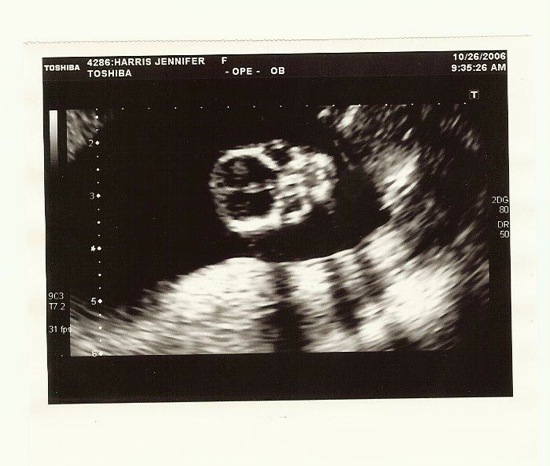

10/27/2006 Scans

BabyHarris4